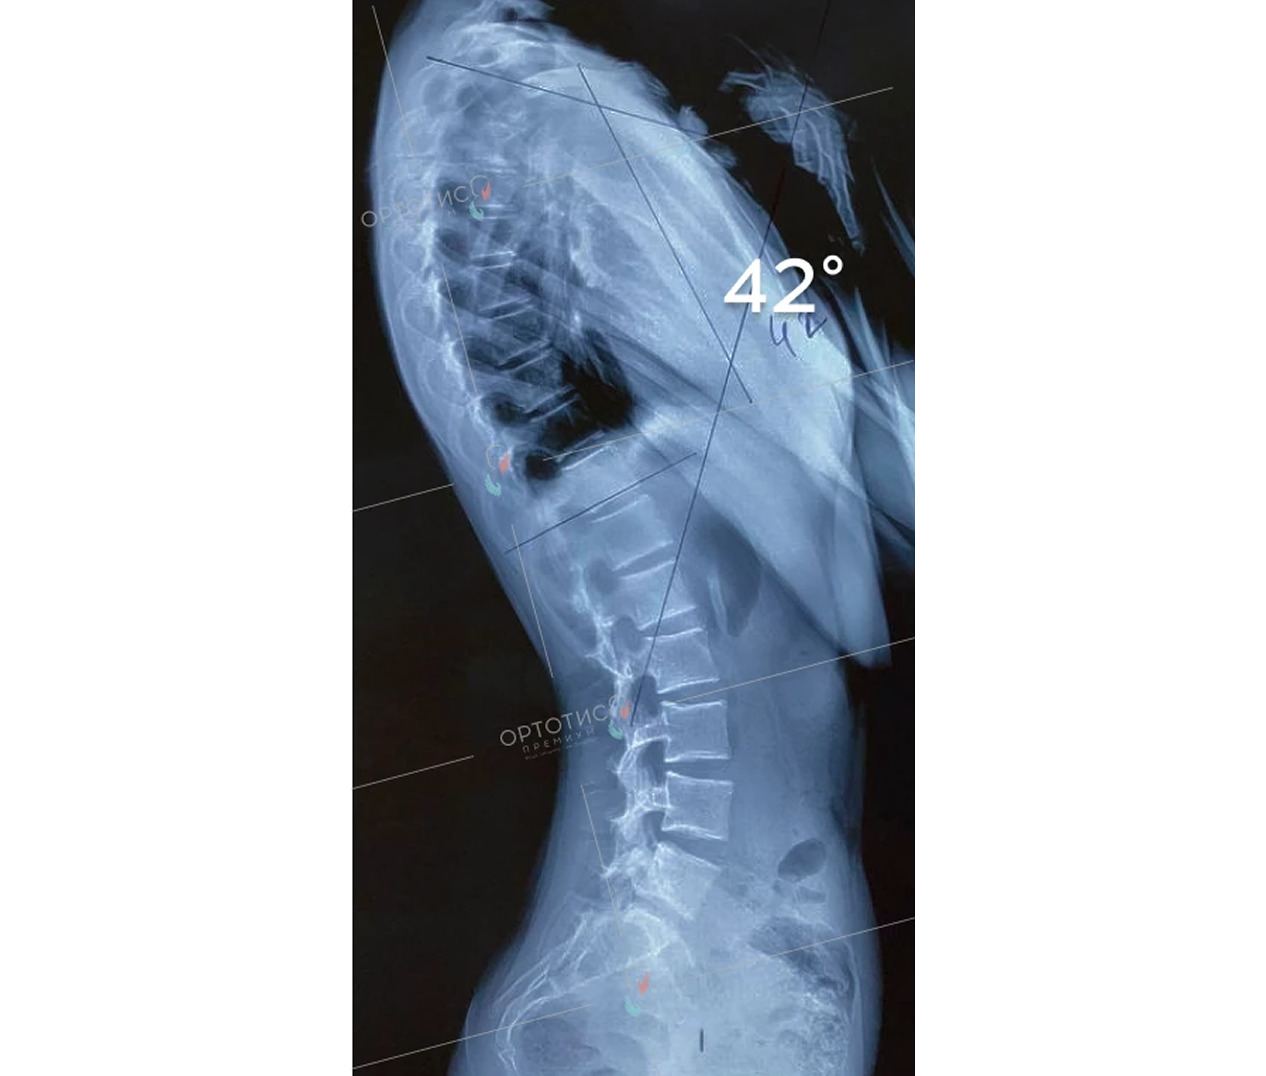

Корсет Шено в Алматы: эффективное лечение сколиоза

Корсет Шено — это «золотой стандарт» в лечении сколиоза у детей и подростков. В клинике Ортотис Центральная Азия в Алматы мы изготавливаем активные ортопедические корсеты, которые не просто удерживают позвоночник, а эффективно исправляют деформацию.

• Идиопатический сколиоз с углом искривления от 20° по Коббу;

• Быстро прогрессирующие формы деформации позвоночника;

• Кифосколиоз и другие нарушения осанки.

Мы используем высокоточное 3D-моделирование, что позволяет создать корсет, идеально соответствующий анатомии ребенка. Это обеспечивает максимальную коррекцию при сохранении мобильности. Наши техники-ортопеды в Алматы проводят регулярную коррекцию изделия по мере исправления позвоночника.